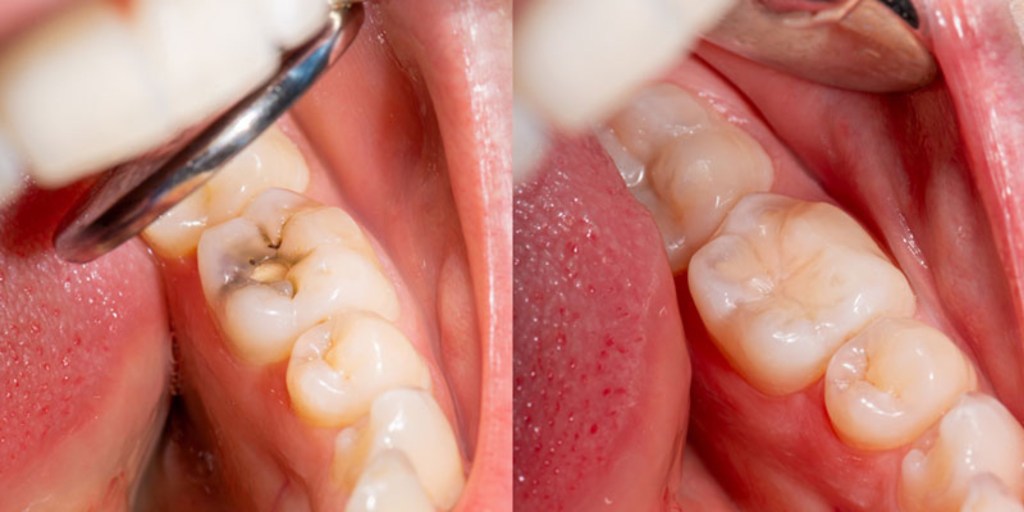

• Tooth-colored fillings for cavities

• Replacement of old or failing restorations

Restorative dentistry focuses on repairing damaged, decayed, or missing teeth to bring back proper function, comfort, and aesthetics. Using modern materials and precise techniques, we help you regain a healthy bite and a natural-looking smile—so you can eat, speak, and smile with confidence again